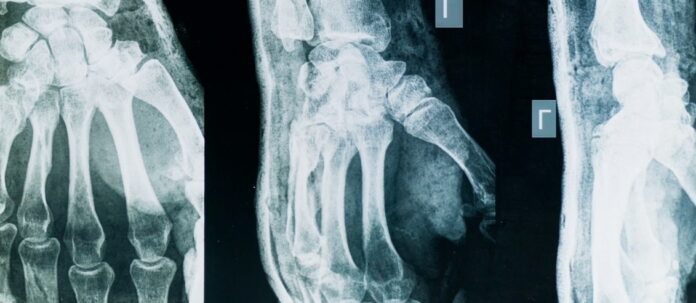

La riflessione di Selmi si sofferma su due aspetti: riconoscimento della malattia e fattori di rischio. “La diagnosi di artrosi si fa tuttora con la semplice radiografia; il consumo di cartilagine di uno dei due capi ossei porta un avvicinamento delle due ossa all’interno dell’articolazione e si ha l’artrite reumatoide, che può essere intercettata prima e trattata con efficacia. La prima localizzazione tipica dell’artrosi è la schiena: se facciamo una radiografia della colonna lombare o cervicale a chiunque abbia più di cinquant’anni troveremo segni di artrosi in tutti, ma per fortuna non tutti ne soffrono; dopo la localizzazione della colonna si passa alle mani. I fattori di rischio più importanti sono per l’artrosi familiarità, genere femminile, età avanzata e sovrappeso, indipendentemente dalla localizzazione; per l’artrite reumatoide familiarità, genere femminile e fumo di sigaretta; per l’artrite psoriasica la presenza di psoriasi”.